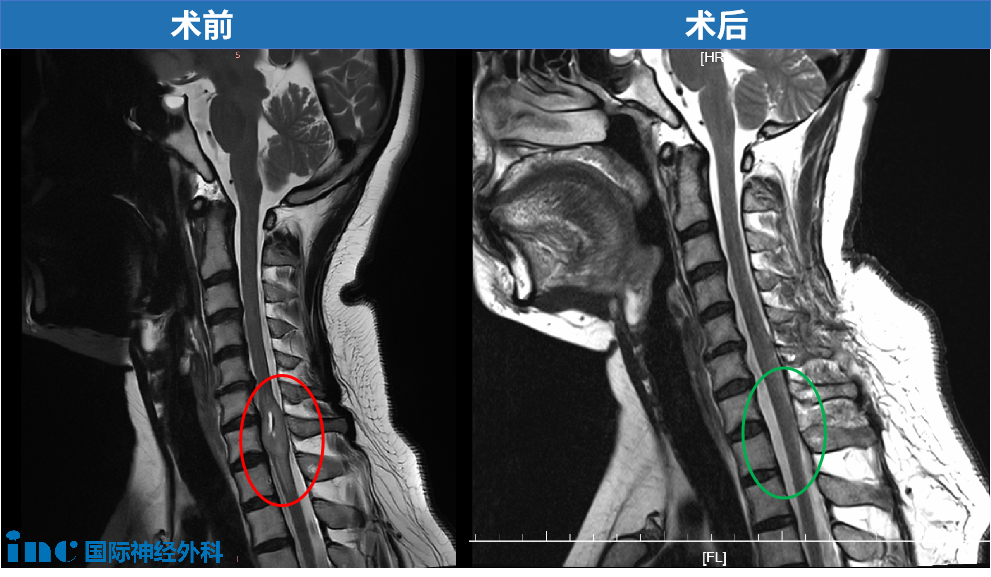

影像学检查结果显示脊髓内存在占位性病变,增强核磁共振确诊为脊髓髓内肿瘤。确诊后患者通过文献查阅了解到该疾病可能导致的神经功能损伤,包括下肢运动功能障碍和大小便控制异常等严重并发症。

在病情恶化后,患者通过医学专著了解到INC巴特朗菲教授在脊髓肿瘤领域的专业经验。经过多渠道资料查阅和深入评估,最终决定接受手术治疗方案。治疗团队采用神经导航系统进行精确定位,成功实施肿瘤全切手术。

术后患者进入ICU监护治疗,第二天神经功能检查显示下肢运动功能保存良好。术后第四天患者可在辅助下进行行走训练,大小便控制功能在术后第二天开始恢复。术后两周随访显示肿瘤完全切除,神经功能得到最大程度保留。